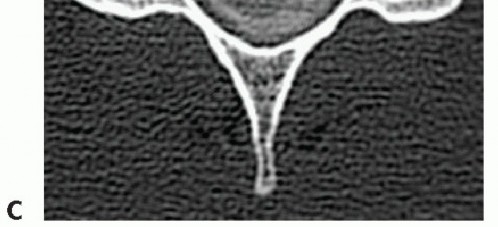

### FIG 1 • OPLL. A. Continuous OPLL causing severe spinal canal stenosis from C1 to C4. B. Axial CT scan in a different patient demonstrating a central stalk of OPLL. C,D. Congenital canal in different patients. Congenital stenosis is defined as a ratio of the canal to the vertebral body of 0.8 or less, and it can be measured on lateral radiographs (C) or advanced imaging such as CT-myelography (D). The CT-myelogram shows superimposed spondylotic changes that further narrow the canal dimensions and cause cord compression.